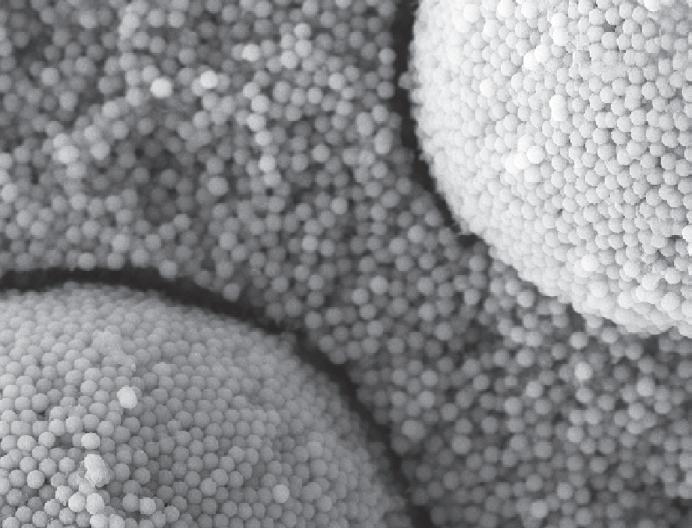

Emerging evidence of the links between the bacteria associated with periodontal disease and cognitive impairment has been a breakthrough in the understanding and potential management of cognitive decline. Increasing evidence has unlocked a greater awareness of some of the specific bacteria involved in Alzheimer’s Disease (AD), the most common form of cognitive impairment, representing 60-70% of all cases. A new study has also revealed some positive effects on brain health associated with a healthy microbiome and the availability of certain chemicals and oral bacteria. In a healthy mouth, there are thousands of distinct microorganisms which colonise specific areas of soft as well as hard tissue. A greater understanding in recent years of these unique oral microenvironments has led to more focused therapies for improving the oral health of patients. Maintaining a diverse oral microbiome is increasingly proven to be key in supporting both oral and systemic health.